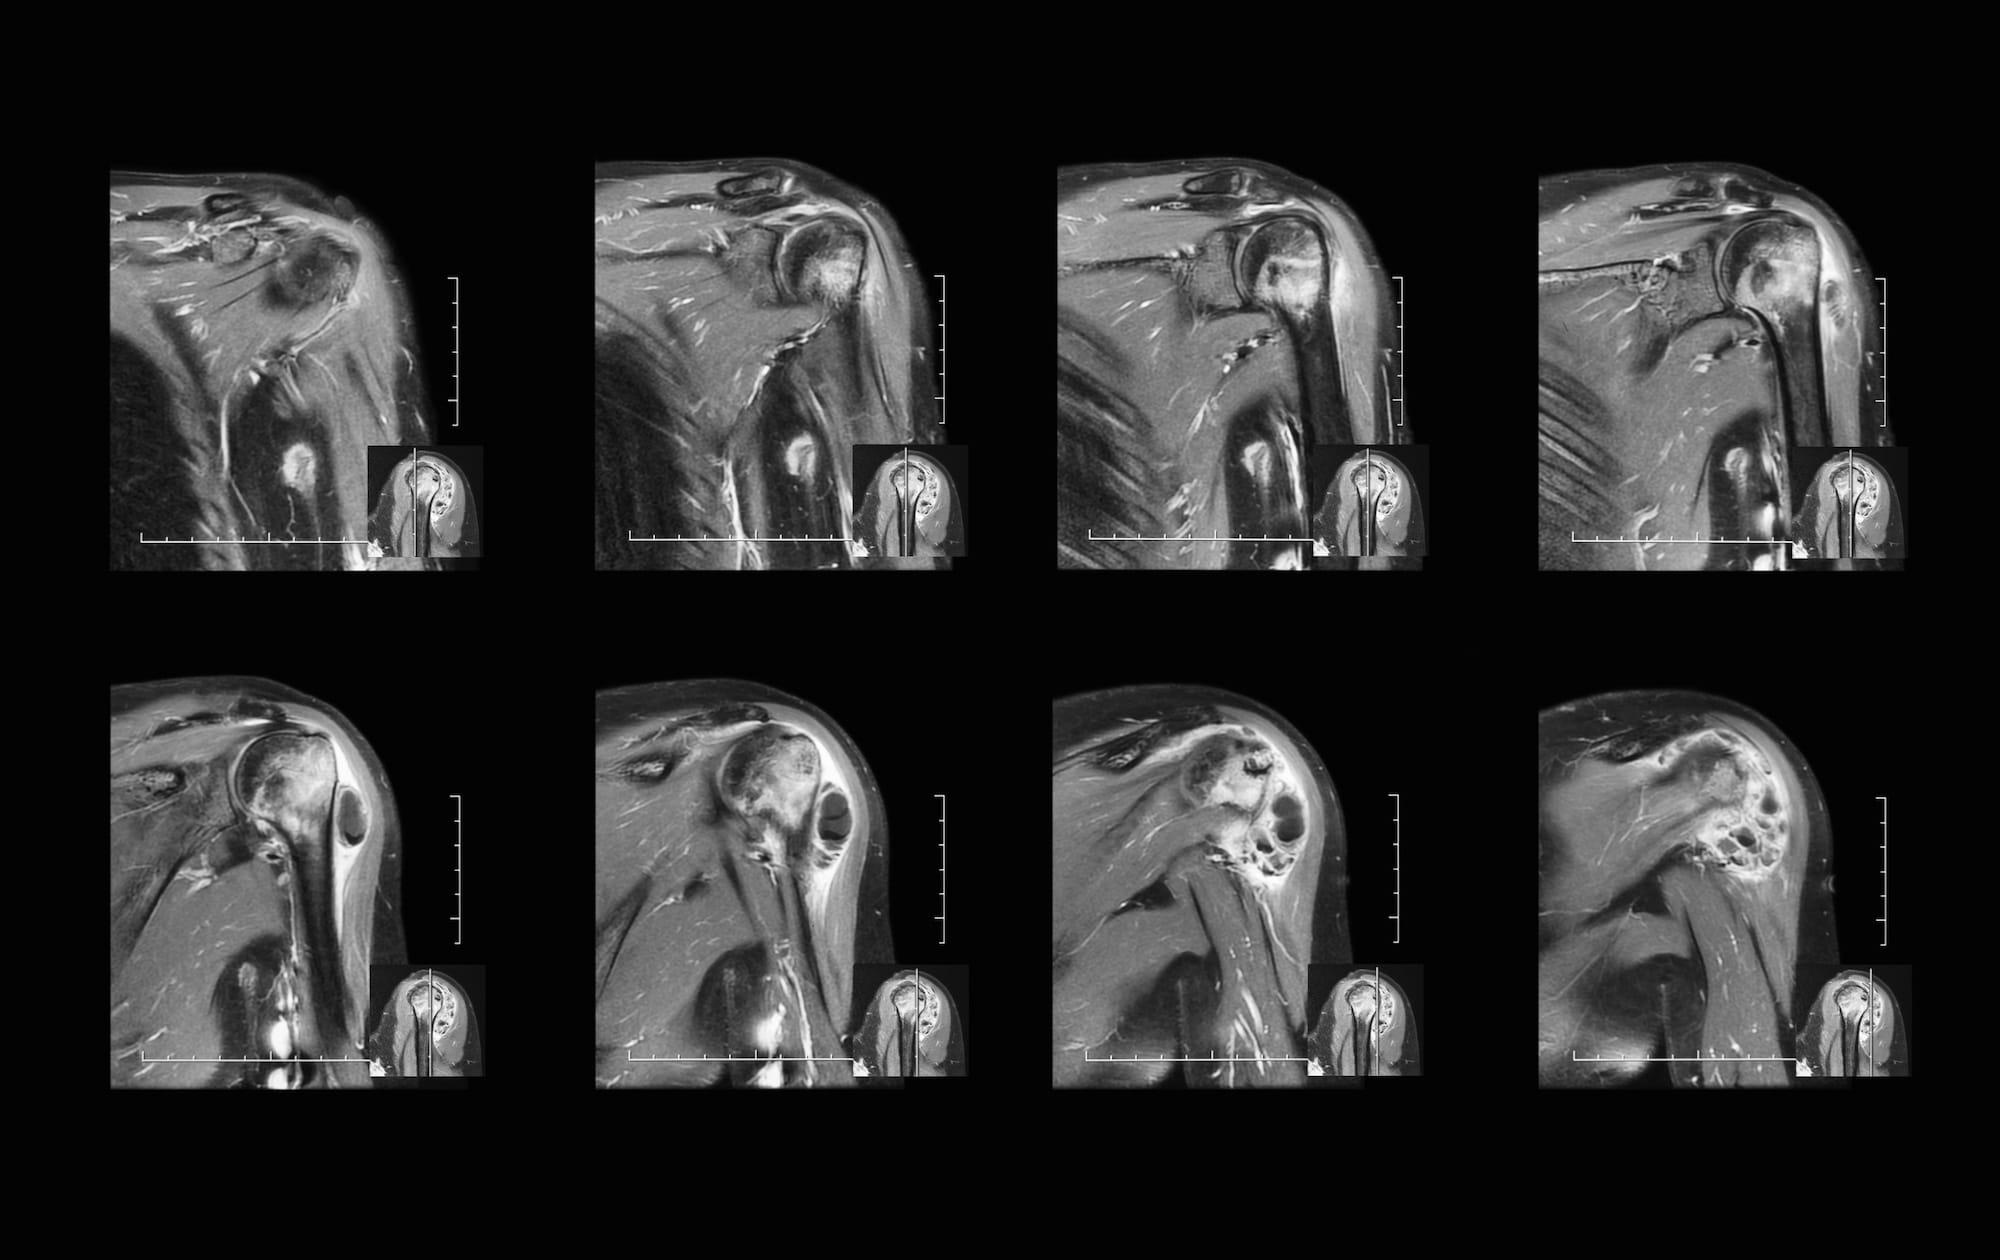

ARTHROGRAM MRI with CONTRAST Stock Image Image of series, joint 193415243 What Is A Shoulder Mri Arthrogram  An mri scan uses magnets and radio waves to capture images of your body’s internal. Mri shoulder arthrography is typically ordered to assess anatomical structures poorly visualized without the. The evaluation of the shoulder, and especially its soft tissue structures, is best done with an mri. What is a shoulder mri scan? The procedure is often followed by a ct. What Is A Shoulder Mri Arthrogram.